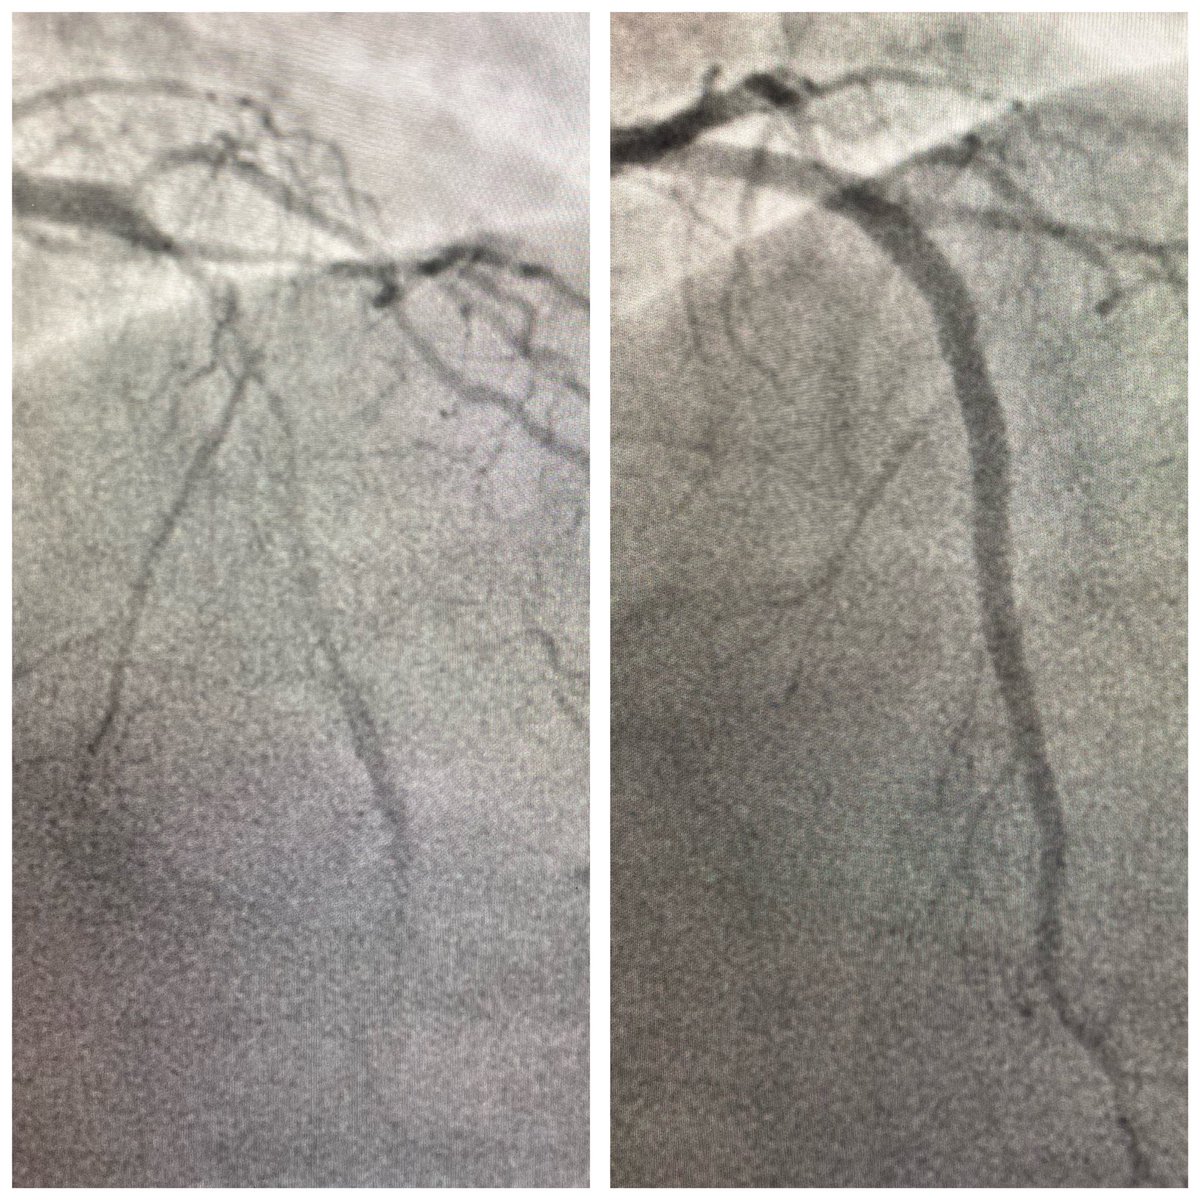

First #RotaPro use in our centre. #ESRD Diffuse heavily #calcified LAD #IVUS near 360 1.5 #burr #170krpm x 5 runs NC 3.0, #DES x2 , NC 4.0 @bostonsci @PCRonline @BotPci Best thing, to view a replay #EuroPCR #Rota session afterward ☕️ #FromBenchToBedside

w_jyg's tweet image. First #RotaPro use in our centre.

#ESRD Diffuse heavily #calcified LAD

#IVUS near 360

1.5 #burr #170krpm x 5 runs

NC 3.0, #DES x2 , NC 4.0